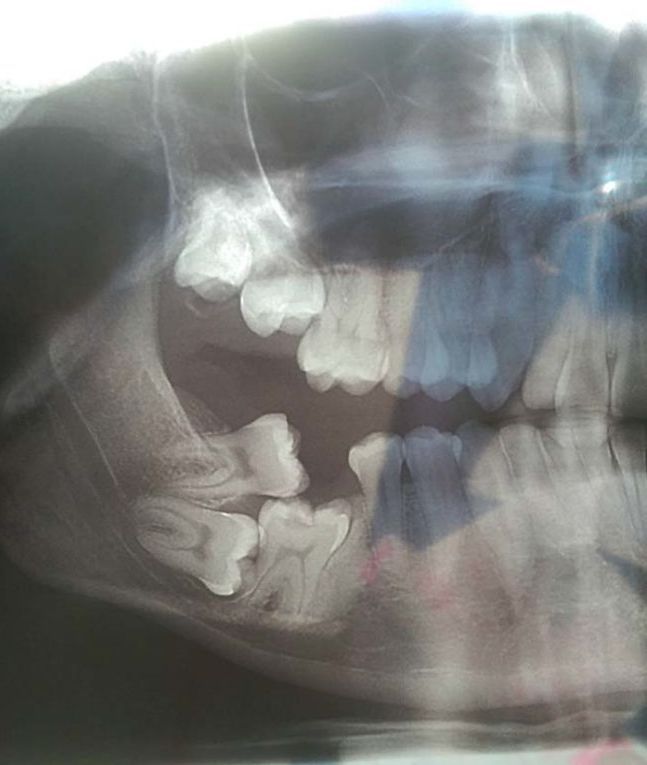

/ 8Zęby mądrości

Ktoś, a raczej coś, bawi się w chowanego.